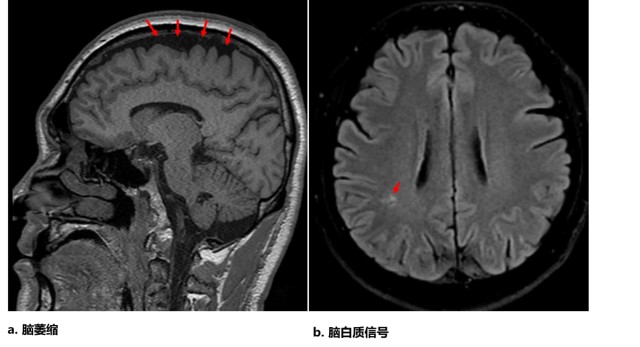

神经影像:颞叶t2wi/flair高信号病变的鉴别诊断

图片尺寸1078x574